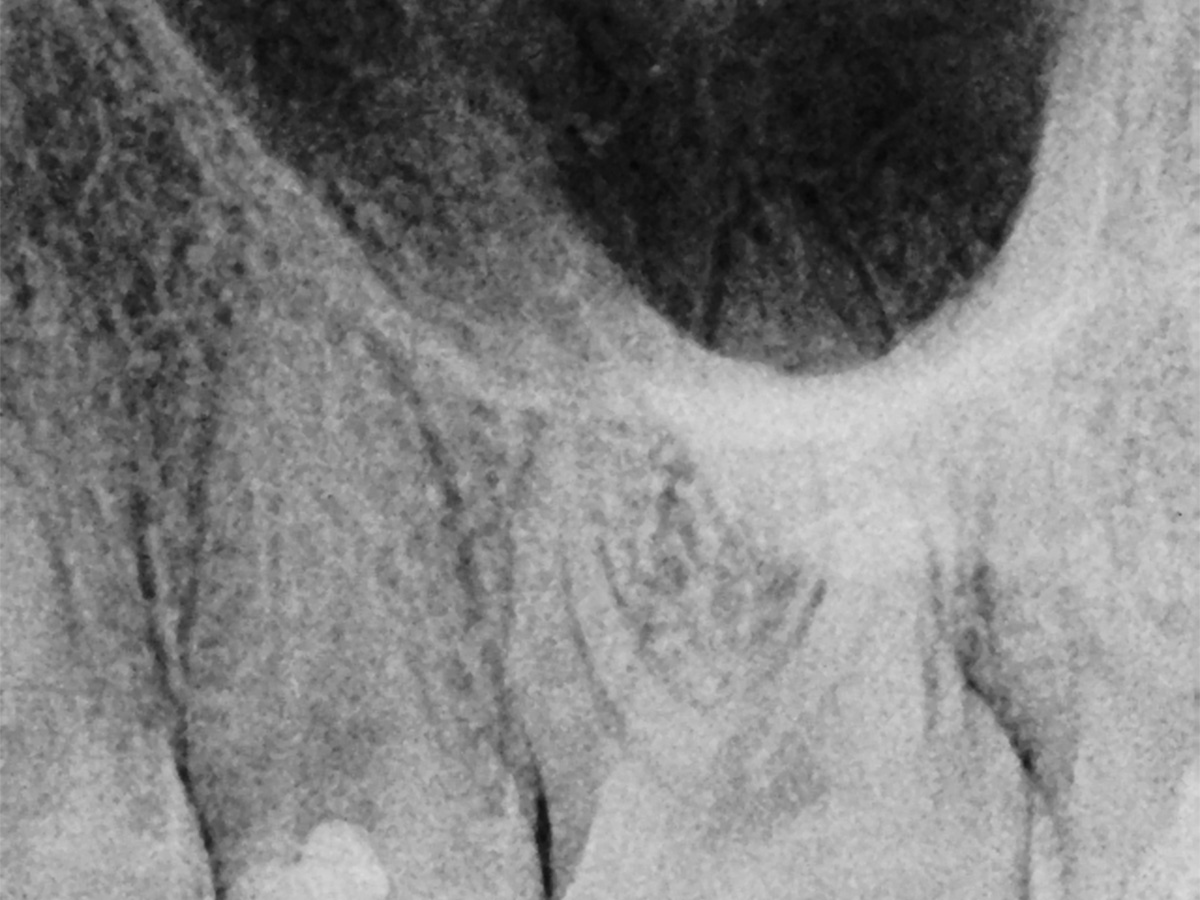

Abbildung 4

Karies grob entfernt.

Abbildung 5

Karies pulpenfern entfernt, Vorbereitung für die Pulpotomie.